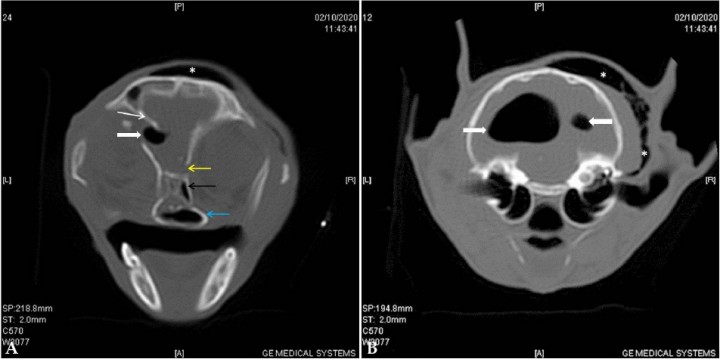

<p>TAC inicial. Cortes transversales en algoritmo de hueso del TAC, adquirido en algoritmo de tejido blando y hueso a 0,6 mm de grosor. (<strong>A</strong>) Corte caudal al seno frontal. Se observa una fractura simple y deprimida en la parte temporal del hueso frontal izquierdo (flecha blanca), desplazamiento de la fosa etmoidal en su unión con el hueso frontal del lado derecho (flecha amarilla), desplazamiento del meato etmoidal y preesfenoides (flecha negra), y fractura simple de la lámina perpendicular derecha del hueso palatino (flecha azul) (<strong>B</strong>) Corte a la altura de las bullas timpánicas que muestra una bóveda craneal íntegra y acúmulo moderado de aire en el tejido subcutáneo de la región temporal izquierda (flechas).</p>

TAC inicial. Cortes transversales en algoritmo de hueso del TAC, adquirido en algoritmo de tejido blando y hueso a 0,6 mm de grosor. (A) Corte caudal al seno frontal. Se observa una fractura simple y deprimida en la parte temporal del hueso frontal izquierdo (flecha blanca), desplazamiento de la fosa etmoidal en su unión con el hueso frontal del lado derecho (flecha amarilla), desplazamiento del meato etmoidal y preesfenoides (flecha negra), y fractura simple de la lámina perpendicular derecha del hueso palatino (flecha azul) (B) Corte a la altura de las bullas timpánicas que muestra una bóveda craneal íntegra y acúmulo moderado de aire en el tejido subcutáneo de la región temporal izquierda (flechas).

El estudio inicial de TAC mostró fracturas múltiples en huesos de la cara, base de cráneo y bóveda.

En la Fig. 1A se muestra una imagen transversal en algoritmo de hueso, caudal al seno frontal, en la que se observa una fractura simple y deprimida en la parte temporal del hueso frontal izquierdo, desplazamiento de la fosa etmoidal en su unión con el hueso frontal del lado derecho, desplazamiento del meato etmoidal y preesfenoides, y fractura simple de la lámina perpendicular derecha del hueso palatino. Además, también se puede constatar la presencia de una lesión hipoatenuante en comparación con el músculo, compatible con aire debajo de los músculos temporales, en mayor cantidad en el del lado izquierdo, en la zona retrobulbar dorso-medial, e intracraneal dorso-lateral izquierdo a modo de neumoencéfalo.

En el resto del estudio, además, se evidenciaron fracturas múltiples deprimidas en la parte orbital del hueso frontal bilateralmente a distintas alturas. También se observó una fractura simple y no desplazada en la lámina horizontal del hueso palatino del lado izquierdo, una fractura simple y deprimida en el maxilar derecho y una fractura no desplazada de la rama mandibular izquierda. Las zonas más caudales del cráneo resultaron sin fracturas (Fig. 1B).